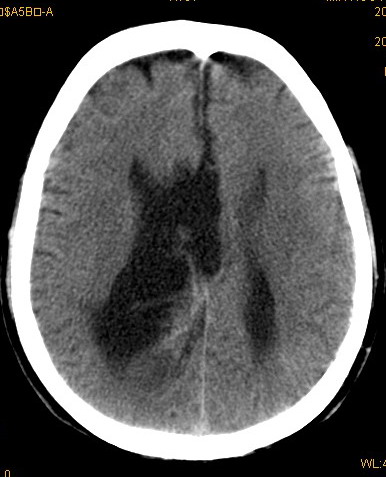

以下是引用卜一在2008-8-14 16:31:00的发言:[br]支持:巨脑回伴脑积水!另:胼胝体发育不良!

以下是引用随光逐影在2008-8-14 16:58:00的发言:[br]胼胝体发育不良;脑积水。

以下是引用同在2008-8-14 19:46:00的发言:[br]巨脑回伴积水,胼胝体发育不良.